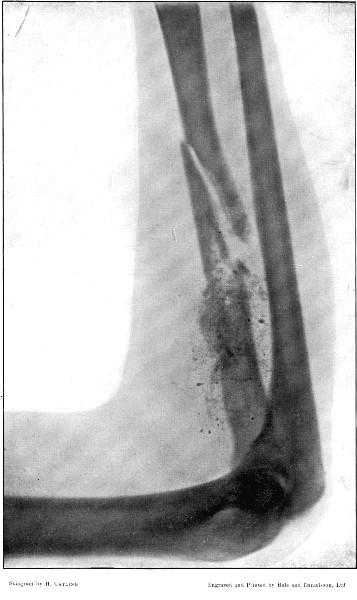

6. Comminuted Fracture of Humerus due to Oblique Impact184

7. Same Fracture healed186